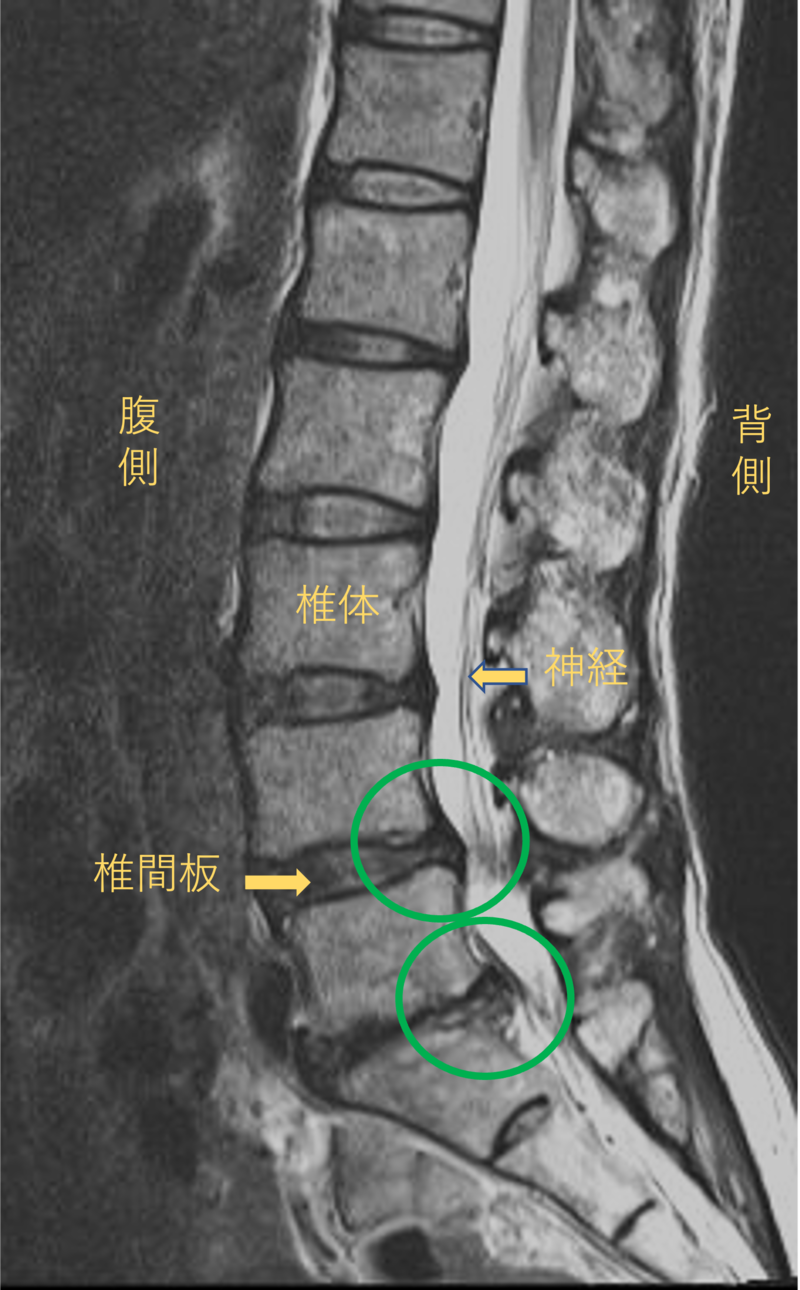

腰を横から見たMRI画像です。

腰椎という骨と骨の間に椎間板と呼ばれるクッションがあります。

このクッションの中身が飛び出す状態が椎間板ヘルニアと呼ばれます。

このMRI画像では、椎間板が背中側に飛び出して足に向かう神経が圧迫されることが痛み、しびれの原因となっておりました。